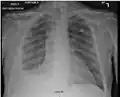

There are three key elements to the diagnosis of silicosis. First, the patient history should reveal exposure to sufficient silica dust to cause this illness. Second, chest imaging (usually chest x-ray) that reveals findings consistent with silicosis. Third, there are no underlying illnesses that are more likely to be causing the abnormalities. Physical examination is usually unremarkable unless there is complicated disease. The examination findings are not specific for silicosis.[20]

For uncomplicated silicosis, chest x-ray will confirm the presence of small (< 10 mm) nodules in the lungs, especially in the upper lung zones. Using the ILO classification system, these are of profusion 1/0 or greater and shape/size "p", "q", or "r". Lung zone involvement and profusion increases with disease progression. In advanced cases of silicosis, large opacity (> 1 cm) occurs from coalescence of small opacities, particularly in the upper lung zones.

With retraction of the lung tissue, there is compensatory emphysema. Enlargement of the hilum is common with chronic and accelerated silicosis. In about 5–10% of cases, the nodes will calcify circumferentially, producing so-called "eggshell" calcification. This finding is not pathognomonic (diagnostic) of silicosis. In some cases, the pulmonary nodules may also become calcified.

Chest X-ray showing uncomplicated silicosis -